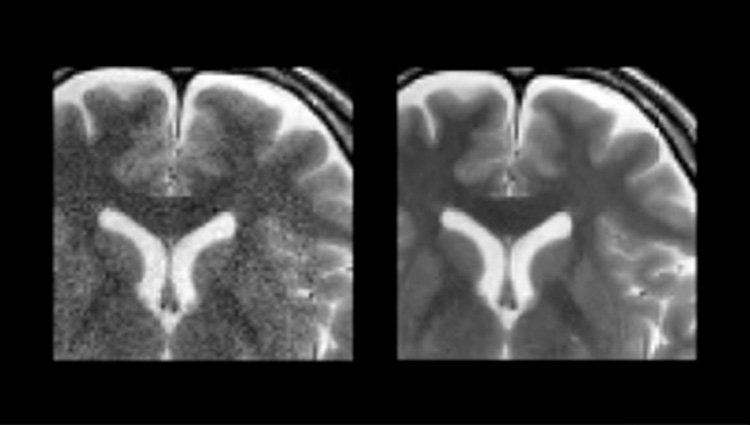

- Mejora de imagen

- Segmentación de la anatomía

- Detección / Diagnóstico

- Soporte de flujo de trabajo